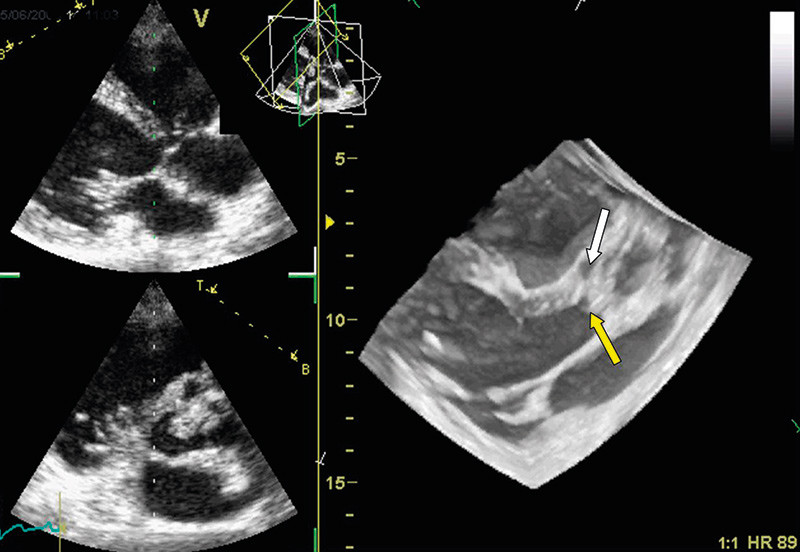

Vurdering av klaffesykdom med bruk av 3D-ekko har vært validert i ulike studier. Foreløpig er det diagnostikk av patologiske mitralklaffer som er best dokumentert (9) – (12). Det har i løpet av de siste ti år foregått en endring i den kirurgiske behandling av mitralklaffsykdom. Nye kirurgiske teknikker har muliggjort reparasjon av mitralfeilen hos mange pasienter som før måtte ha klaffeerstatning. Slik reparativ kirurgi stiller strenge krav til presis diagnostikk av mitralklaffens form og funksjon, slik at riktig kirurgisk metode kan anvendes. Pasienter med mitralklafflekkasje utredes hos oss med 3D-ekko for nøyaktig lokalisering av klaffens skade (fig 2). Vi har spesiell nytte av det såkalte kirurgiske innsyn (surgeons view) fra venstre atrium, hvor hele mitralklaffen kan fremstilles i samme bilde som vist i figur 2.

I dag er todimensjonal transoesophagusekkokardiografi påkrevd før kirurgisk teknikk velges ved behandling av mitralprolaps. Interessant nok er det nylig vist at tredimensjonal utvendig ekkokardiografi (transtorakal) var likeverdig med todimensjonal transoesophagusekkografi i lokalisering av mitralklaffprolaps (10). Tredimensjonal transoesophagusekkografi var enda mer presist i diagnostikken av kommisurale prolapser, som kan være vanskelige å reparere. Dette er viktig informasjon for planlegging av kirurgisk metode ved valg av ventil versus klaffebevarende, reparativ kirurgi. Ved en rekke hjertekirurgiske sentre i Europa gjøres det nå rutinemessig 3D-ekko før mitralklaffplastikk.